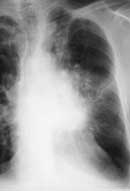

Рис. 1. Рак левого верхнедолевого бронха с переходом на главный. (а) Обзорная рентгенограмма в прямой проекции

Рис. 1. Рак левого верхнедолевого бронха с переходом на главный. (б) Цифровая томограмма.

Рис. 1. Рак левого верхнедолевого бронха с переходом на главный. (в) Компьютерная томограмма. Конгломерат опухоли и левых паратрахеальных лимфоузлов врастает в легочную артерию. Метастазы в паратрахеальные лимфоузлы справа.

Таким образом, совершенно очевидно, что выбор тактики лечения, прогноз и выживаемость больных определяются в первую очередь состоянием регионарных лимфоузлов. По мнению ряда авторов, выявление увеличенных лимфоузлов корней легких достигается при обычной томографии (точность 92%). Существенным преимуществом томографии является возможность адекватного отображения трахеи, трахеобронхиального угла, карины, главных бронхов. Наиболее информативным неинвазивным методом определения метастазов в лимфатических узлах средостения на сегодняшний момент является компьютерная томография (КТ). Поэтому совершенно необходимо выполнение этого исследования до начала лечения (Рис. 1). Величина медиастинальных лимфоузлов достаточно точно коррелирует с частотой их поражения. H. Nishiyama и соавт. считают, что метастазы отсутствуют в узлах диаметром менее 1 см. При диаметре 1.1 — 1.5 см возможно поражение узлов. Диаметр более 1.5 см указывает на регионарные метастазы. По данным авторов, при таких установках точность КТ до операции составляла 78%, специфичность — 79%. Однако и с помощью компьютерной томографии нельзя дифференцировать метастазы от гиперплазии лимфатических узлов или их увеличения, связанного с обтурационным пневмонитом. В таких условиях данные КТ следует оценивать с большой осторожностью. В связи с этим некоторые авторы рекомендуют считать пораженными узлы диаметром более 20 мм, неизмененными — менее 10 мм. При узлах 10 — 20 мм в диаметре возникает подозрение на метастазы.